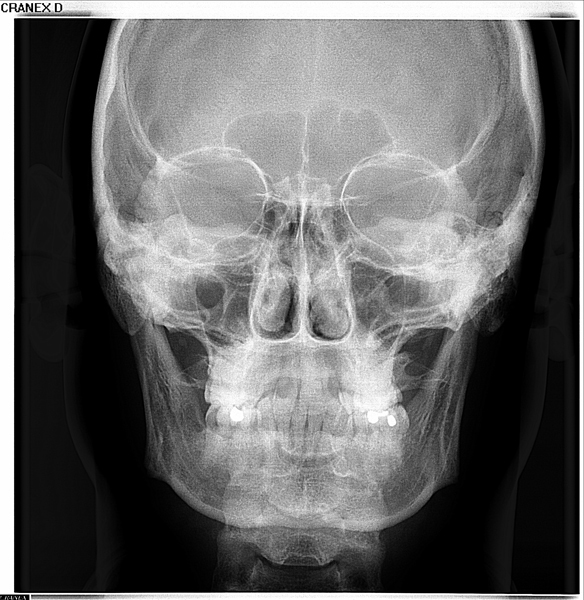

Telerradiografia Frontal